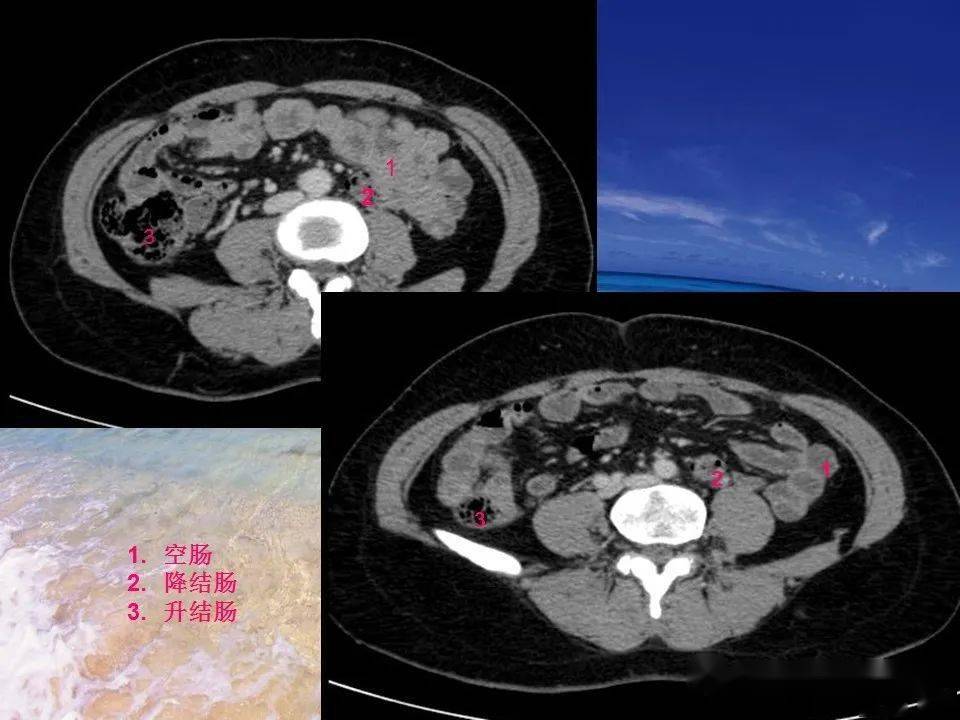

根据你对胃肠道解剖位置的了解,请1~4 分别为哪个胃肠道的

图片尺寸1080x810